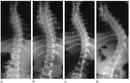

Her bir tür, farklı tedavi yaklaşımları gerektirebilir. İdiyopatik skolyoz, genellikle ergenlik döneminde ortaya çıkar ve tedavi edilmediğinde ciddi sorunlara yol açabilir. Skolyozun TanısıSkolyozun tanısı genellikle fizik muayene ve görüntüleme yöntemleri ile konur. Doktor, hastanın duruşunu değerlendirir ve gerekirse röntgen çekimi yapar. Röntgen, omurganın eğilimini ve açılarını belirlemeye yardımcı olur. Skolyoz Tedavi YöntemleriSkolyoz tedavisinde kullanılan başlıca yöntemler şunlardır: